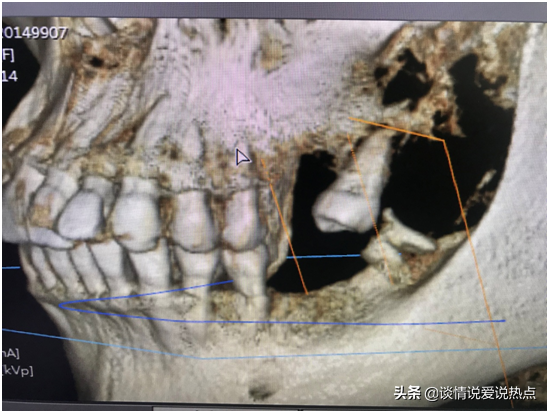

下圖是我現(xiàn)在左邊的牙齒,下頜有一顆殘根,要拔掉,上頜由于缺牙太久,旁邊那顆已經(jīng)歪得很?chē)?yán)重,看到它歪成這樣我自己都被嚇到。從遠(yuǎn)期果考慮,醫(yī)生建議拔掉再種,不然下頜種上了兩顆,與這顆的咬合關(guān)系是擁擠的,咀嚼不力,咬合關(guān)系不好,長(zhǎng)期使用就會(huì)受影響。加上這顆牙齒有齲壞,經(jīng)過(guò)深入的考慮,我還是決定拔掉種了。